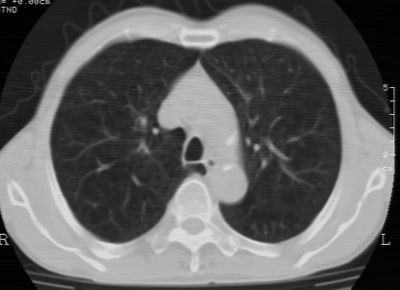

标题: CT24783:m71,既往肺心病史3年,现咳嗽,憋喘。 [打印本页]

标题: CT24783:m71,既往肺心病史3年,现咳嗽,憋喘。

1、左肺上叶spn,毛刺+分叶+血管集束征,考虑周围型肺癌可能性大

2、全小叶性肺气肿。

1)左肺上叶周围型肺癌可能。2)两肺全小叶型肺气肿。

左上周围型肺癌,全小叶型肺气肿。